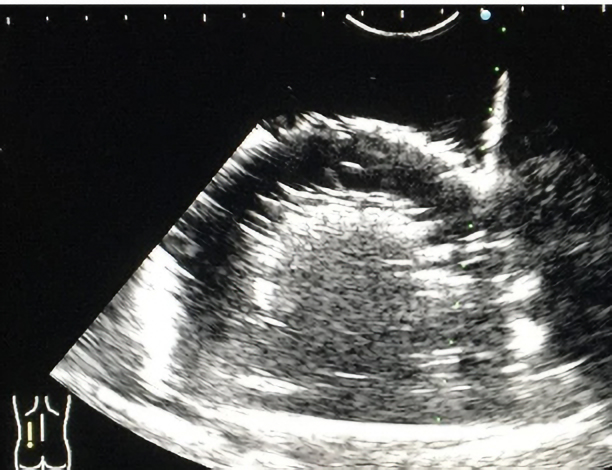

作製したモデルは、超音波下で腎臓の皮質・髄質に該当する部分のコントラストは実際の腎臓のものに類似しており、針穿刺の際にモデル内に針が侵入する様子が超音波下で観察可能です。本モデルの検証のため、岡山大学病院の腎生検経験20例未満の研修生10名に腎生検模擬を実施し、腎生検経験20例以上の腎生検に熟達した腎臓内科医20名がその様子を観察あるいは模擬を実施しました。また、腎生検模擬後に全参加者にアンケート調査を実施しました。その結果、90%の研修生が今回の腎生検模擬によって患者への腎生検に対する不安が軽減されると回答しました。

作製したモデルは、超音波下で腎臓の皮質・髄質に該当する部分のコントラストは実際の腎臓のものに類似しており、針穿刺の際にモデル内に針が侵入する様子が超音波下で観察可能です。本モデルの検証のため、岡山大学病院の腎生検経験20例未満の研修生10名に腎生検模擬を実施し、腎生検経験20例以上の腎生検に熟達した腎臓内科医20名がその様子を観察あるいは模擬を実施しました。また、腎生検模擬後に全参加者にアンケート調査を実施しました。その結果、90%の研修生が今回の腎生検模擬によって患者への腎生検に対する不安が軽減されると回答しました。